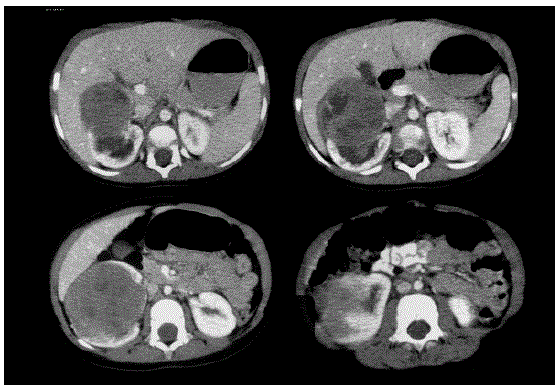

Menino de 3 anos, apresenta episódios de hematúria macroscópica há 2 meses, total, sem coágulos e indolor. Mãe nega alterações do hábito intestinal, febre e perda de peso. A criança não apresenta comorbidades. Nasceu de termo, parto normal, sem intercorrências.

Ao exame físico, apresenta-se em BEG, corado e hidratado. Peso, altura e DNPM normais para a idade

Abdome: globoso, indolor e sem massas palpáveis.

Genitália externa: normal. Testículos tópicos

Durante a investigação, foi submetido, entre outros, ao exame mostrado a seguir.

Baseado no exposto, assinale a alternativa correta. O diagnóstico mais provável e a melhor forma de tratamento para este paciente são, respectivamente: